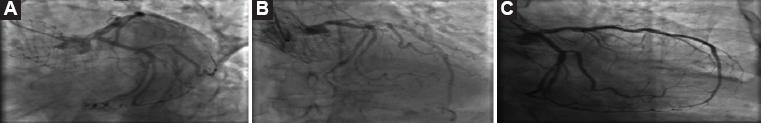

Cardiac catheterization was performed 6 days after admission, (Fig. 4) finding an anterior descending artery with calcified lesion with 60% severity, rest of the permeable vessel without significant lesions, TIMI flow grading system 3, circumflex with irregularities, stent in marginal branch with 40% neointimal hyperplasia TIMI 3 distal flow, left dominance, and non-dominant right coronary artery without lesions. Despite the findings, the lesion in the anterior descending artery does not coincide with the alterations found in the echocardiogram or the EKG, thus confirming the diagnosis of SCM or Takotsubo syndrome.

Figure 4 Cardiac catheterization. A: left anterior oblique caudal. B: AP cranial (anteroposterior). C: right anterior oblique caudal (right anterior oblique).